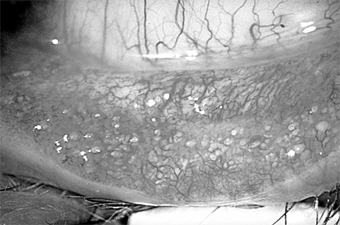

Ocular rosacea is a common complication of acne rosacea and probably occurs more often in light-skinned people, especially of Irish descent, than in dark-skinned people. It is usually a blepharoconjunctivitis, but the cornea is sometimes also affected. The patient complains of mild injection and irritation. There is frequently an accompanying staphylococcal blepharitis. The blood vessels of the lid margins are dilated and the conjunctiva hyperemic, especially in the exposed interpalpebral region. Less often, there may be a nodular conjunctivitis with small gray nodules on the bulbar conjunctiva, especially near the limbus, which may ulcerate superficially. The lesions can be differentiated from phlyctenules by the fact that even after they subside, the large dilated vessels persist.

Microscopic examination of the nodules shows lymphocytes and epithelial cells. The peripheral cornea may ulcerate and vascularize, and the keratitis may have a narrow base at the limbus and a wider infiltrate centrally. The corneal pannus is often segmented or wedge-shaped inferiorly (Figures 5-16 and 5-17).

Figure 5-16

Figure 5-16: Chronic conjunctival injection and inferior keratopathy of rosacea. Note inferior pannus and corneal scarring suggestive of staphylococcal hypersensitivity.